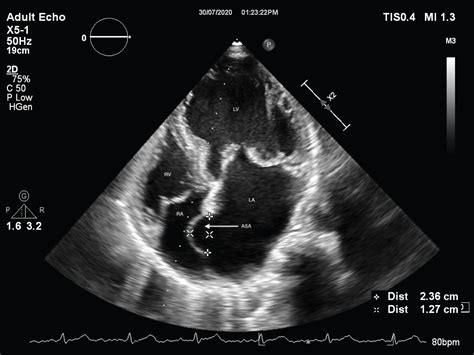

• Echocardiogram: This ultrasound test provides detailed images of the heart's structure and function, allowing doctors to visualize the aneurysm.

• Transesophageal Echocardiogram (TEE): This more invasive procedure involves inserting a probe down the throat to get a clearer view of the heart's structures.

Atrial Septal Aneurysm occurs when the interatrial septum, the wall dividing the left and right atria, becomes thin and weak, causing it to bulge. This bulging can affect the heart's ability to pump blood efficiently and may lead to other cardiac issues. The condition is often asymptomatic, making it difficult to detect without proper medical evaluation.